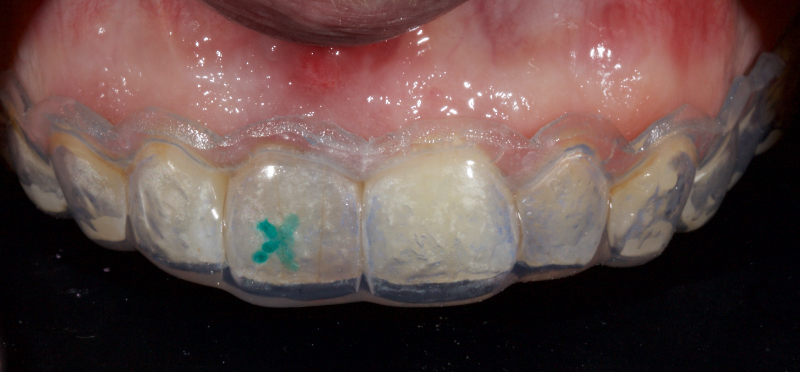

Historically, discolored anterior teeth were treated with indirect ceramic restorations, such as crowns or veneers. This can be illustrated in the case shown in Figure 1, where the discolored left central incisor (2.1), along with two other incisors, was treated with lithium disilicate ceramic veneers (Fig. 2). More recently, direct composite materials that incorporate specialized “opaquers” have also been utilized for treatment.